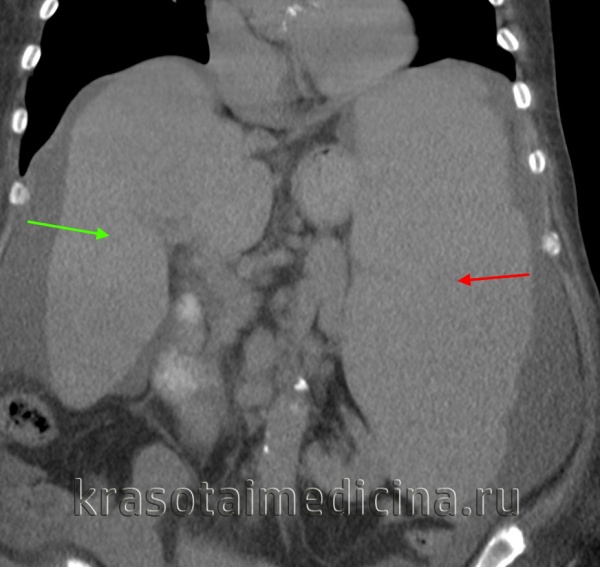

КТ ОБП. Диффузное увеличение печени (зеленая стрелка) и более выраженное увеличение селезенки (красная стрелка).